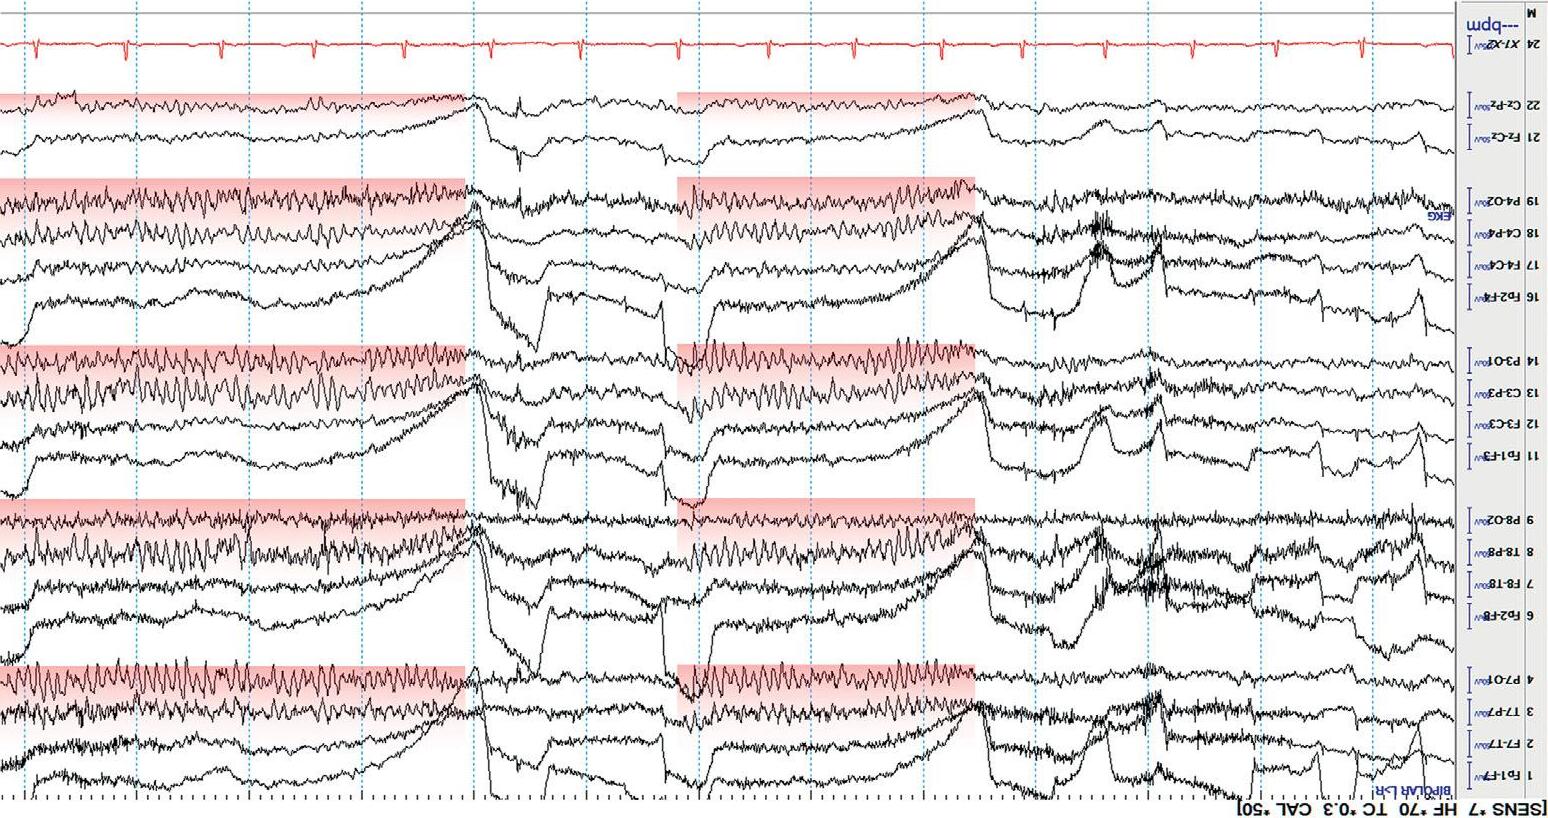

Mostdisplaysshow10or15secondsperpageofEEG. Figure1.5 showsa typicaldisplayusingthelongitudinalbipolarmontagewithexcessivemuscle artifactbefore(a)andafter(b)applicationof30Hzhighfrequencyfilter.

Figure1.5(a) EEGwithHFFsetto70Hz.

Figure1.5(b) ThesameEEGwithHFFsetto30Hz.